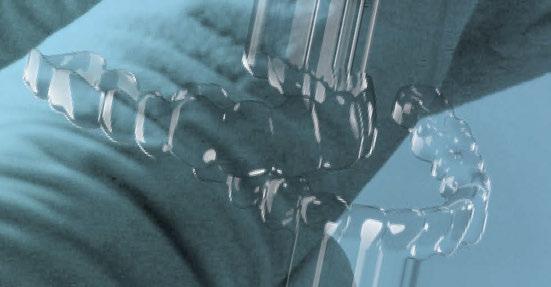

Impartido por los doctores Manuel Román, Federico Hernández- Alfaro y Juan Carlos Pérez-Varela

Aprende en qué casos operar y qué técnica quirúrgica elegir. Conoce a fondo la cirugía ortognática, en el plano vertical y Sagital, cirugía segmentada vs SARPE.

Te enseñamos cómo confeccionar una férula quirúrgica digital y un ClinCheck o Approver de cirugía ortognática. Aprenderás sobre protocolo y planificación y te daremos consejos y soluciones para quepuedas abordar incluso los casos más complejos.